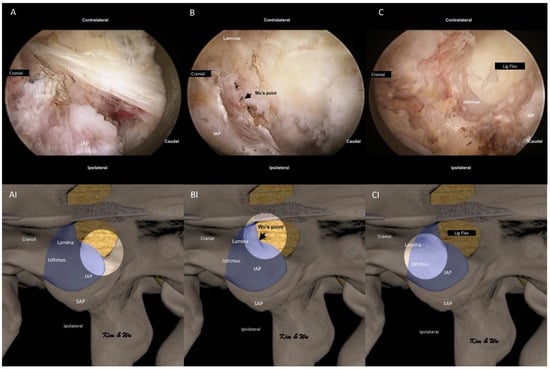

2.2. Endoscopic Surgical Anatomy of Inferior Articular Process in Endoscopic Fusion

2.4.2. Handling of Inferior Articular Process: ETLIF (I) versus ETLIF (O)